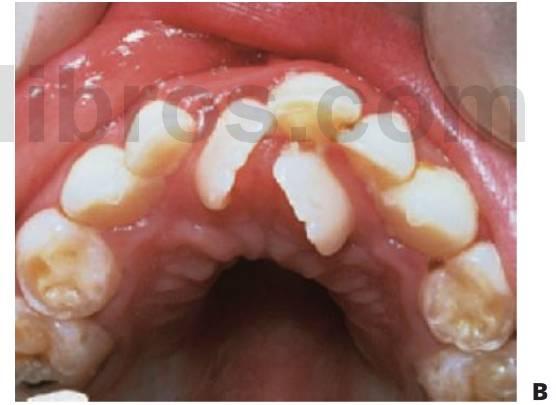

En los casos con apiñamiento, la pérdida de los caninos temporales debería tratarse colocando un arco lingual fijo para mantener los incisivos y evitar su lingualización ya que las líneas medias se corrigen por sí solas.

Cuando los caninos permanentes hacen erupción, puede precisarse realizar el desgaste de la superficie mesial de los primeros molares temporales para posteriormente, cuando erupcionan los primeros premolares, proceder al desgaste de la superficie mesial del segundo molar temporal.

Extracción seriada